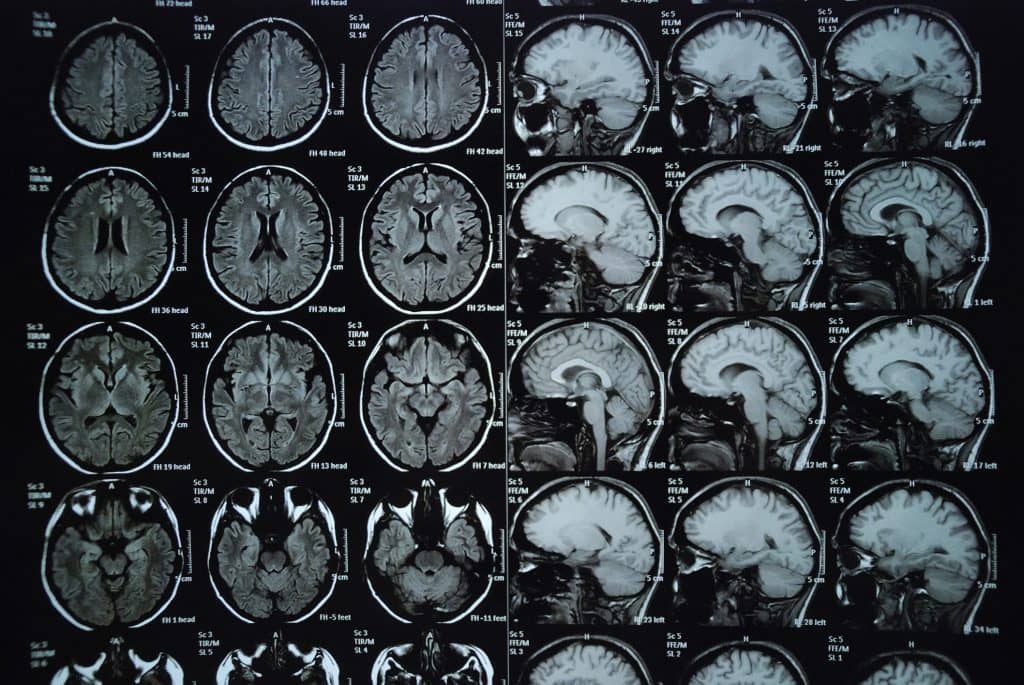

Brain MRI IMED Radiology Network Braces In Mri Machine However, one consideration regarding braces and mri involves the potential for image distortion. Orthodontic brackets are considered to be 'mri safe' but their stability should be meticulously checked and their proximity to the. Magnetic resonance imaging (mri) is. If you have detachable metal braces or a retainer, you should take them out before you get an mri. No, the mri. Braces In Mri Machine.